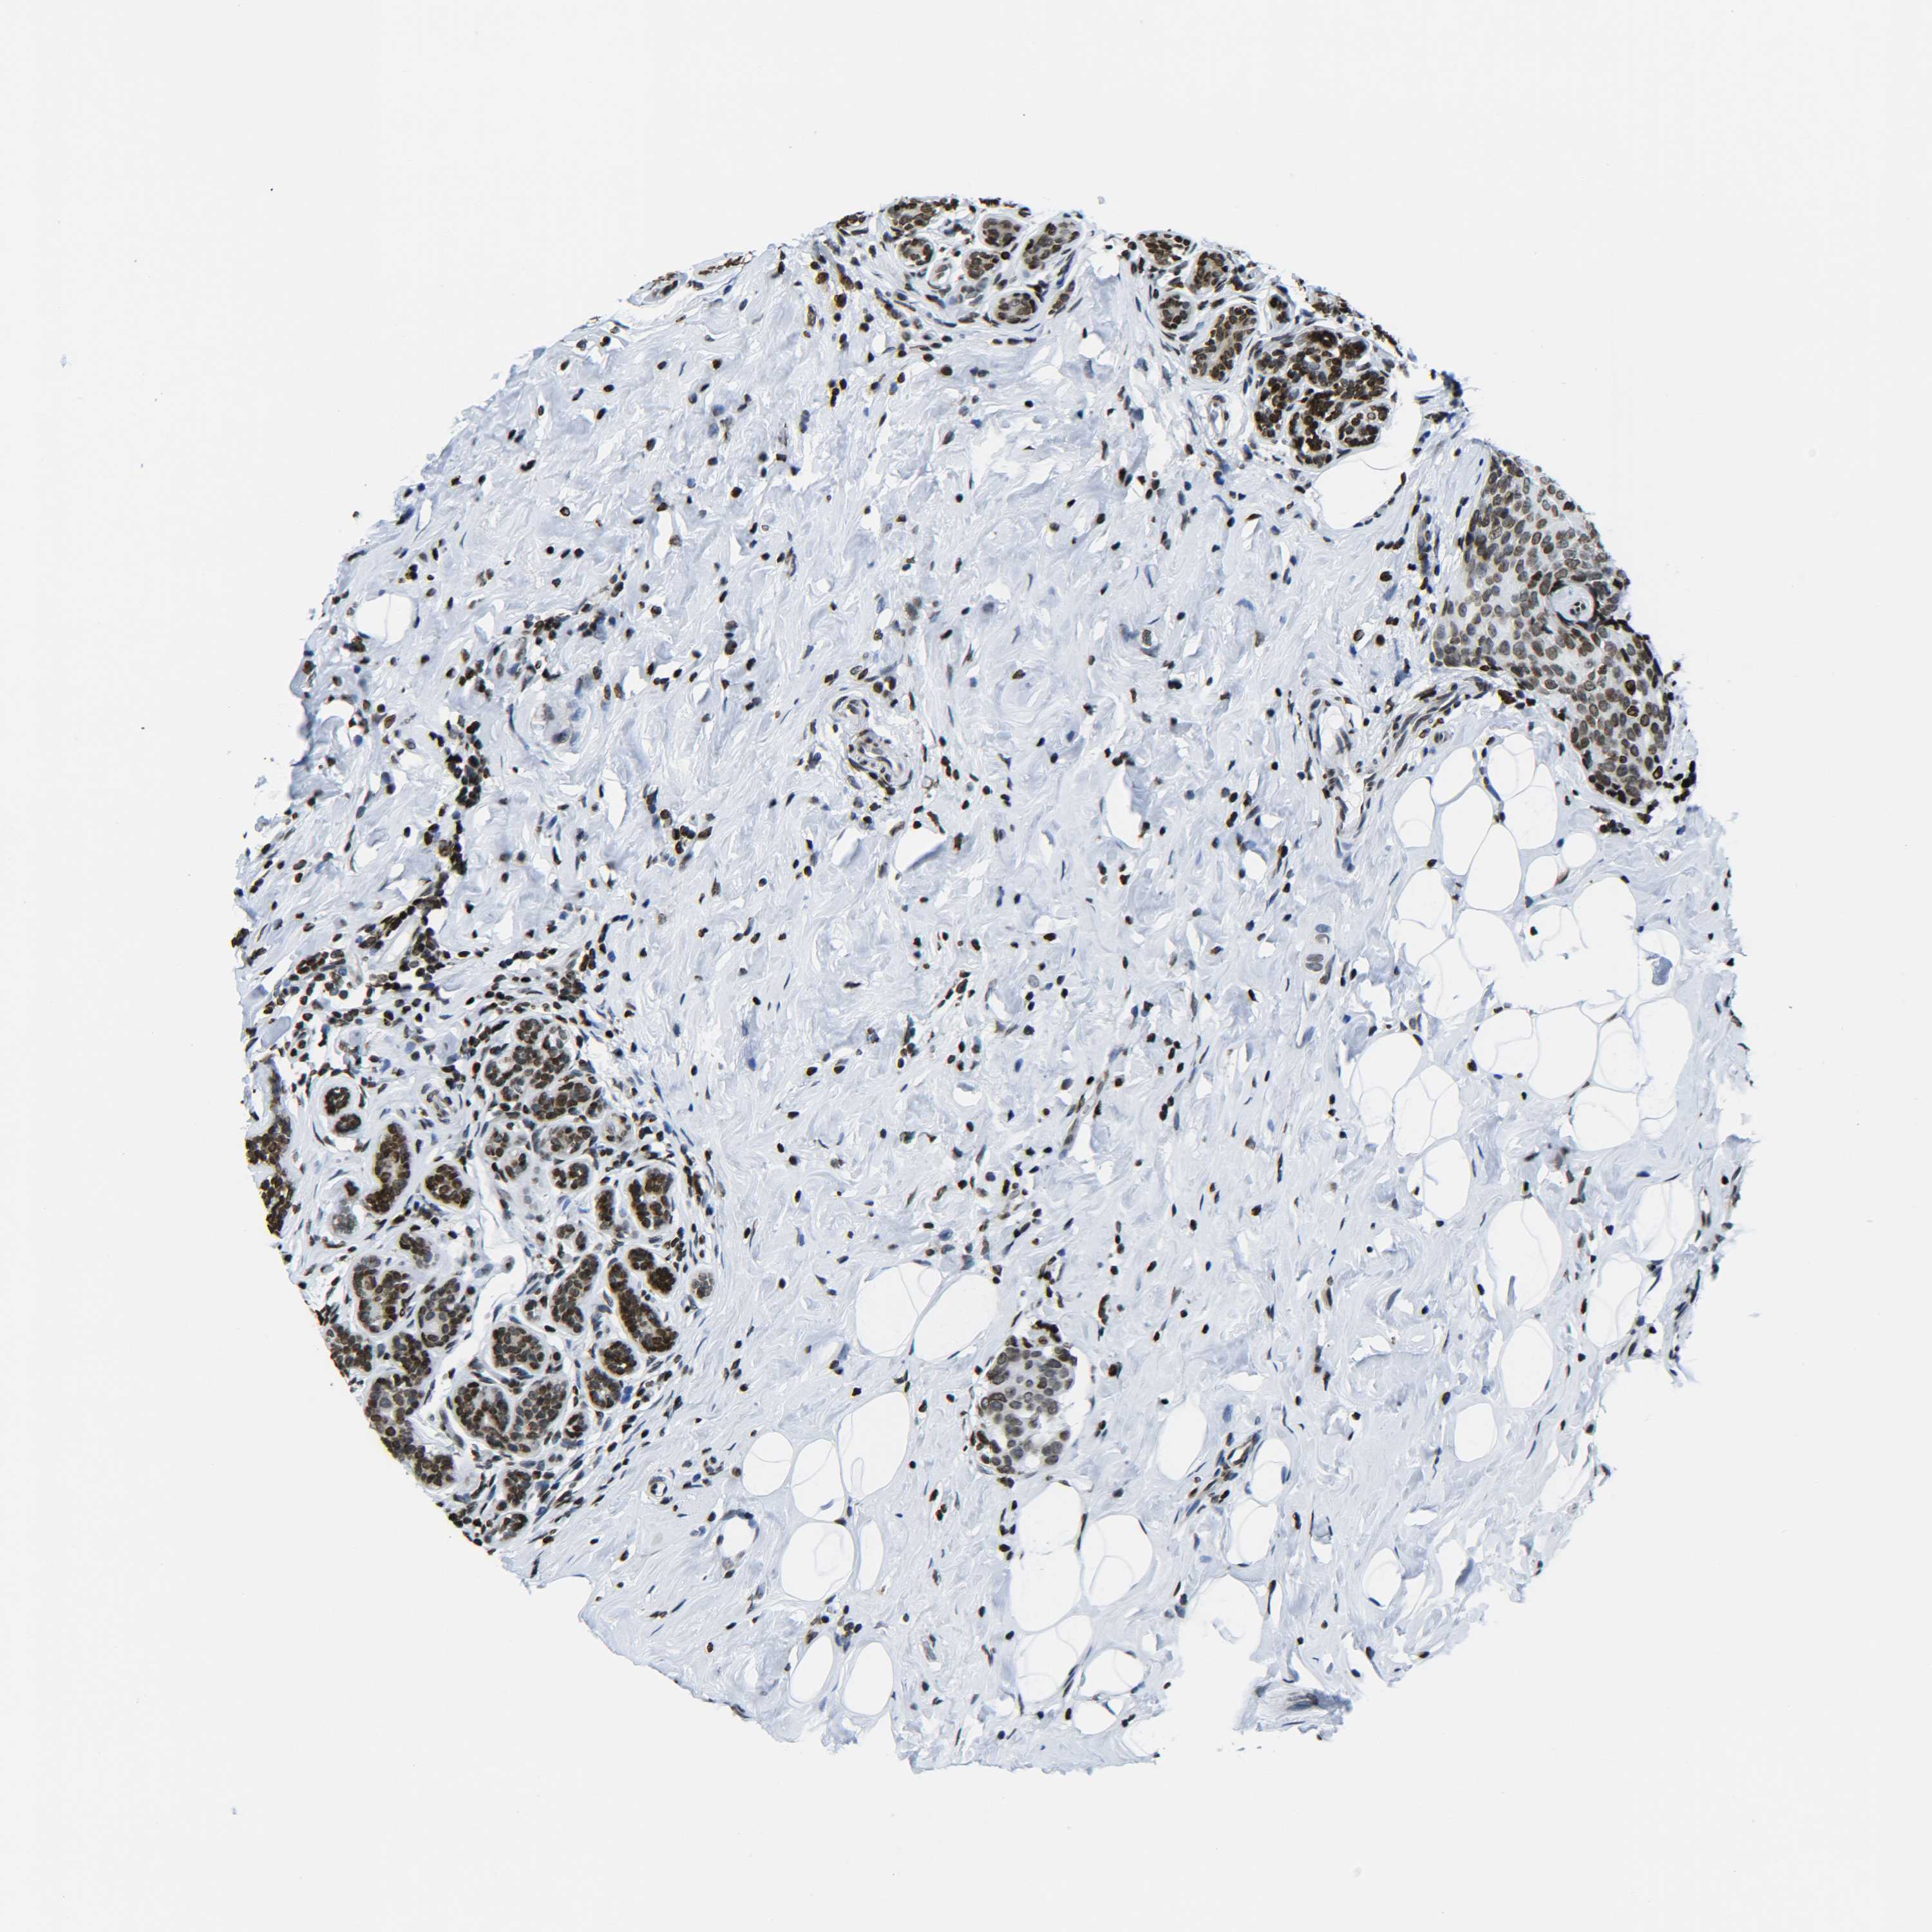

CANCER BREAST CANCER Show tissue menu

BRCA TCGA BRCA VALIDATION PROTEIN EXPRESSION